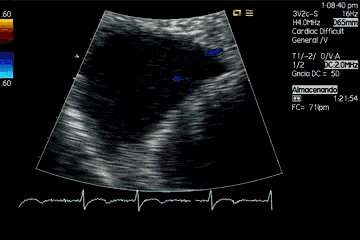

Pero sin duda, hay dos patologías “protagonistas” de este plano en este abordaje. La primera es la visualización de comunicaciones interauriculares (ya sea por CIA verdadera o por foramen oval permeable), como puedes ver en el clip 16.

But undoubtedly, there are two pathologies «protagonists» of this plane in this approach. The first is the visualization of interatrial communications (either by true CIA or permeable foramen ovale), as you can see in clip 16.